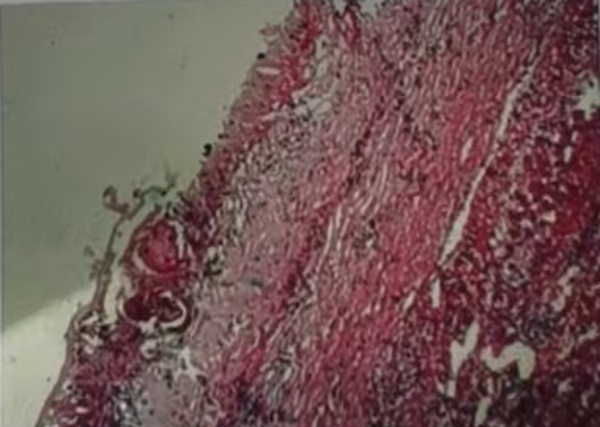

11月19日术中联合控制中心静脉压,Pringle法间断阻断肝门,精准定位外囊与肝组织的界限,避免损伤门脉分支及胆管等重要结构,保持囊壁完整性,术中出血约100ml,成功行“肝左叶S3切除,右叶包虫外囊摘除术”。术后患者恢复良好,病理为:外囊完整囊性肿物,内有粉皮样物,符合包虫病。